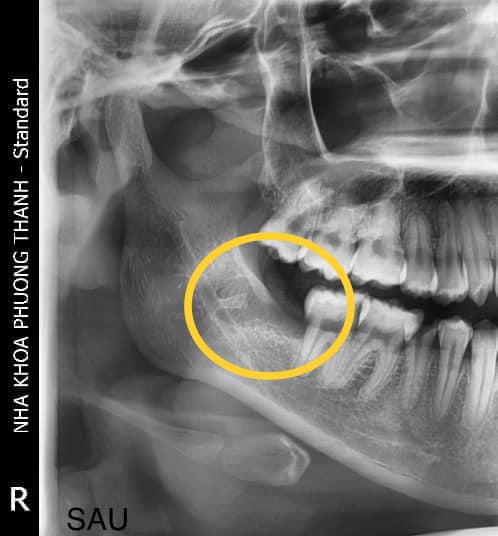

Việc thăm khám và chụp phim giúp bác sĩ đánh giá chính xác vị trí, hướng mọc và mức độ ảnh hưởng của răng khôn, từ đó đưa ra hướng xử lý phù hợp và an toàn hơn.

Thăm khám và điều trị răng khôn tại Nha khoa Phương Thành

Tại Nha khoa Phương Thành, các trường hợp răng khôn sẽ được bác sĩ thăm khám kỹ lưỡng kết hợp với phim chụp đánh giá vị trí răng và cấu trúc xương hàm trước khi đưa ra chỉ định điều trị. Việc kiểm tra đúng thời điểm giúp phát hiện sớm các vấn đề liên quan đến răng khôn và hỗ trợ lựa chọn phương án xử lý phù hợp hơn cho từng trường hợp.